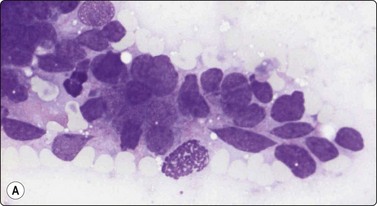

Squamous cell carcinoma (Fig. 14.13)

Scrape smears are a simple way of diagnosing squamous cell carcinoma of the skin, particularly ulcerated lesions. Inflammatory crust and any surface keratinous layers must first be carefully removed to obtain diagnostic cells from the deeper layers. The technique is described above. Nodular and deeply invasive tumors and recurrences are better examined by FNB.

image image

Fig. 14.13 Squamous cell carcinoma

(A) Aggregate of pleomorphic, obviously malignant cells with dense squamoid cytoplasm and distinct cell borders; no obvious keratinization in this field; FNB smear from ulcerated 10–15-mm tumor lower lip (MGG, HP); (B) Cohesive tissue fragment of malignant squamous epithelial cells; scrape smear from ulcerated skin tumor (Pap, HP).

Cytological criteria of squamous cell carcinoma are described in several other chapters, mainly in Chapter 8. The differential diagnosis between well-differentiated squamous carcinoma with cystic degeneration and branchial and other benign cysts lined by squamous epithelium can cause problems due to subtle squamous cell atypia in the former and reactive atypia and metaplasia in the latter (see Chapter 4). Distinction between keratotic basal cell carcinoma and basaloid squamous cell carcinoma can be difficult.4 Cytological criteria for basal cell carcinoma are listed below. The cytomorphology of adenoid (acantholytic) squamous cell carcinoma can cause problems.44 Distinction between in situ (dysplastic solar keratosis, Bowen’s disease) and superficially invasive carcinoma is not possible in smears.